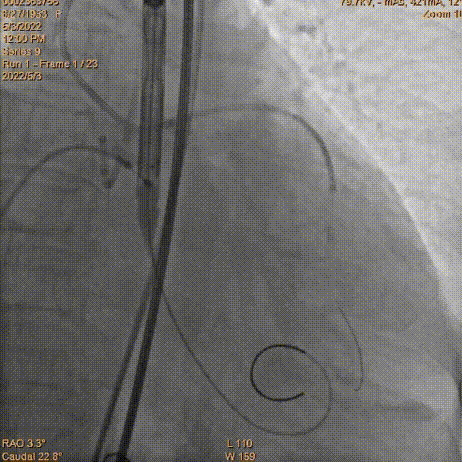

瓣膜定位

工作位造影